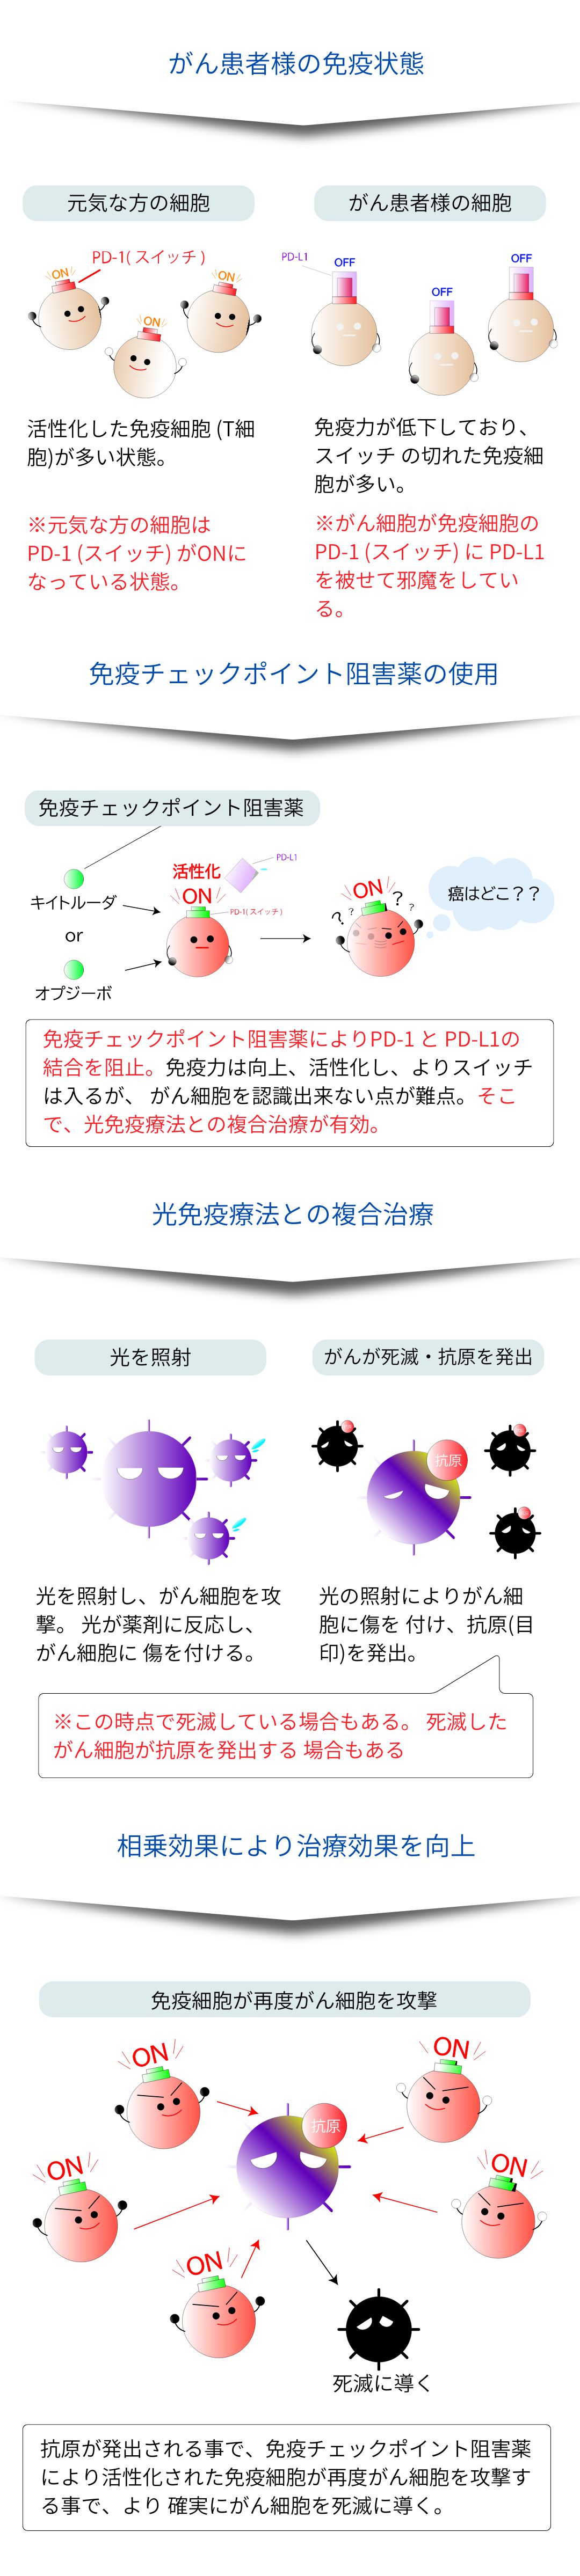

この治療方法では、破壊されたがん細胞から放出される抗原が免疫を活性化するため、照射部位以外の転移巣にも効果をもたらす可能性があります。

効果を向上させる複合治療

- 光免疫療法による腫瘍細胞の死と抗原の放出は、免疫システムを「目覚めさせる」効果があります。これにより、通常は「見過ごされがち」な腫瘍細胞に対する免疫システムの識別能力が向上します。

- PD-1阻害剤による介入は、この「目覚めた」免疫応答が腫瘍細胞に作用するための障害を取り除きます。つまり、光免疫療法で活性化された免疫応答が、PD-1阻害剤によりさらに強化され、効率的に腫瘍を攻撃することができるようになります。

これらの理由から、光免疫療法とPD-1阻害剤は組み合わせて使用すると、単独で使用する場合に比べて腫瘍に対する攻撃力が強化される可能性があります。